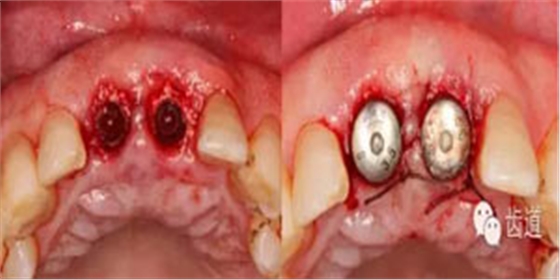

備洞完成

植入種植體(唇側(cè)留2-3mm jumping gap)

確定植入深度(齦下3-4mm)

小直徑愈合基臺(tái)就位后唇側(cè)植骨

更換大直徑愈合基臺(tái)